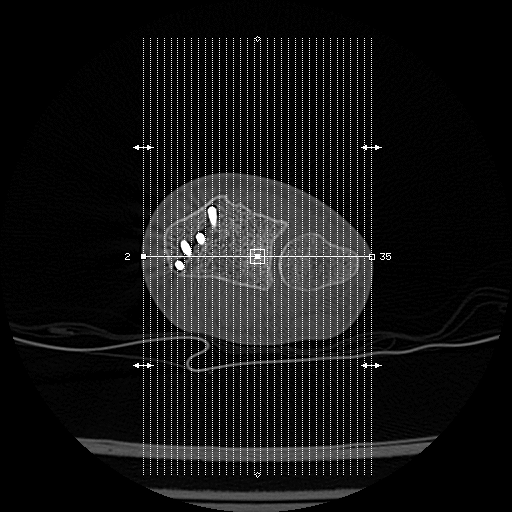

That's my femur. I've also got metalwork in my right hand but i don't get any effects from that at all.

If we're showing off battle scars!

[img]

[/img]| https://thumbsnap.com/0rs741Mk [/img]

[/img]| https://thumbsnap.com/EieDYRsY [/img]

Elbow plate came out a couple of years ago, but still bloody aches, especially in the cold. Wrist is still in there, only gives me gip now and again, usually when I've been carrying heavy stuff about.

As an aside, I had an MRI on it once to see if there were any floating chips of bone around, and managed to blag a CD of the scan, which is pretty much a bunch of images. You can make some funky animated gifs of your innards with them!